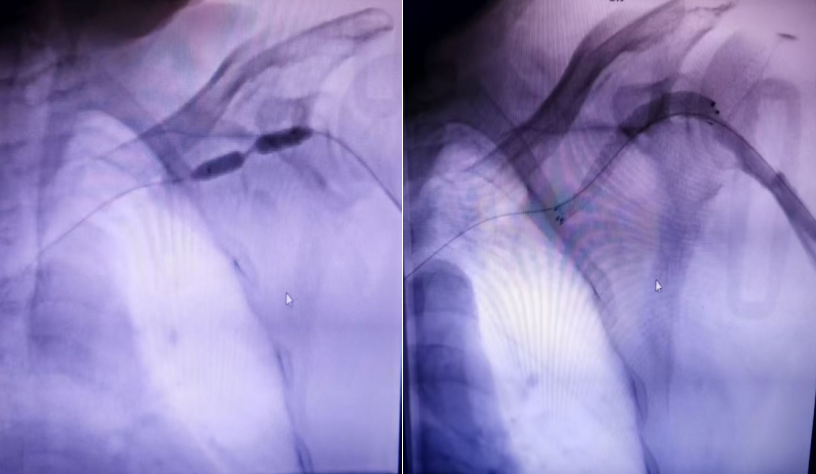

近日,怀化市中心医院(怀化市肿瘤医院)鹤城院区肾病内科团队为一名尿毒症内瘘闭塞患者,成功实施了DSA引导下PTA后Covera覆膜支架植入术。

DSA引导下PTA后Covera覆膜支架植入术

11月19日,11年血液透析患者杨先生从县城来到怀化市中心医院(怀化市肿瘤医院)鹤城院区肾病内科就诊,他因突发血栓导致动静脉内瘘完全闭塞,无法正常进行透析,且杨先生在近几年来已进行过多次球囊扩张手术,传统的单纯球囊扩张术(PTA)虽能短期扩张打开狭窄病变,但对于内膜增生严重、合并钙化且弹性回缩明显的狭窄病变,效果往往不理想,需要植入支架撑开狭窄病变部位的内瘘血管。

面对这一棘手难题,科主任陆小军主任医师带领血管通路团队仔细研讨评估后,为杨先生实施了一项更为先进的技术——PTA后Covera覆膜支架植入术。术后,杨先生立即恢复正常的血液透析,无并发症,内瘘震颤、搏动良好,并顺利度过围手术期,康复出院。